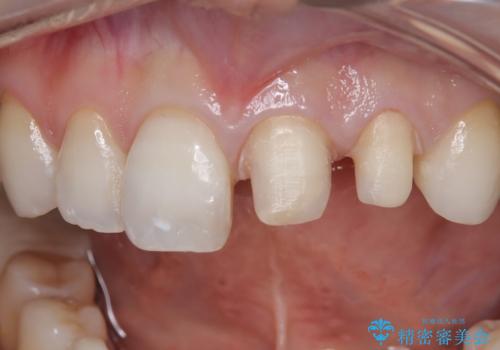

- 「前歯の色が気になる」を主訴に来院された患者さんです。以前他院にて、前歯2本をCR(プラスチック)で治療されていたところが劣化し変色していました。歯の長さも左右で異なっている状態でした。大部分がCR(プラスチック)修復されていたので、オールセラミッククラウンで治療を行いました。

古いCR(プラスチック)とその下の虫歯を除去した後に新しい土台を立てています。適合が良い被せ物を作るために拡大鏡を使用しながら歯を削り、変形のほとんどないシリコンという材料で型取りを行っています。